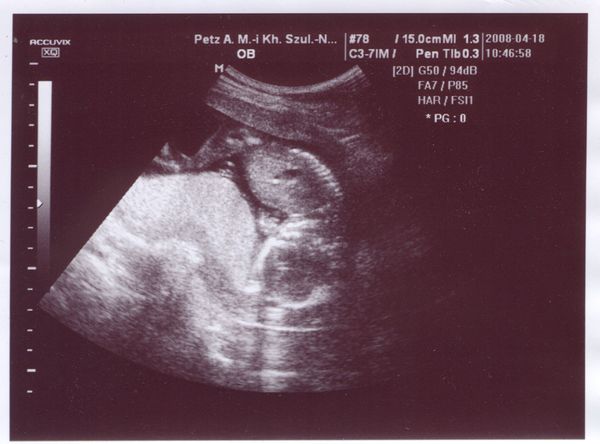

Szépen fejlődik a babóka. Szerintem mostmár csak pozitív dolgokra gondolj, ahogy az elején!